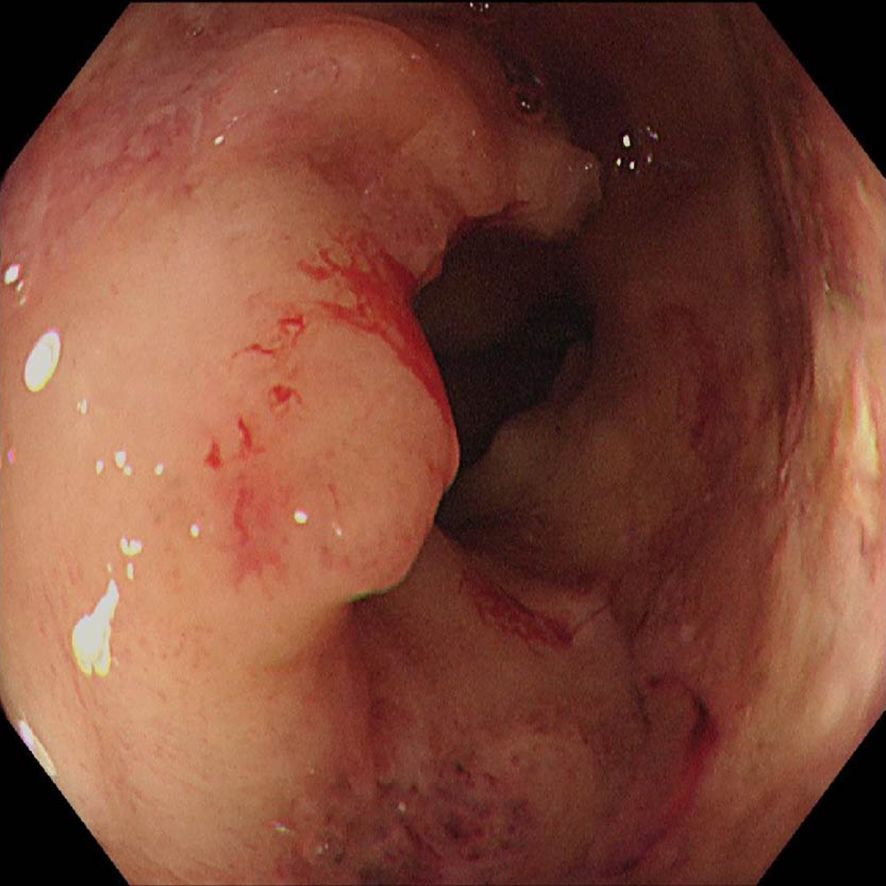

Gastric and colorectal cancers present significant therapeutic challenges, particularly in the elderly population, who often have comorbidities and diminished tolerance to standard treatments. This report describes an 85-year-old male with concurrent stage III gastric adenocarcinoma and stage IIIb microsatellite stable colorectal cancer, who declined both surgery and chemotherapy. Subsequently, the patient was treated with an innovative regimen consisting of endoscopic intratumoral injections of Oncolytic adenovirus H101 in combination with the PD-1 inhibitor tislelizumab. Following this combined therapeutic approach, the patient demonstrated notable tumor shrinkage and downstaging, accompanied by a reduction in serum tumor markers, including CEA and CA19-9. Additionally, there was an observed increase in CD8⁺ and CD4⁺ T-cell counts, indicating systemic immune activation. The treatment was well-tolerated, with the only reported adverse event being mild fever. The patient achieved nearly 4 months of progression-free survival and a substantial improvement in quality of life. This case highlights the potential of combining oncolytic virotherapy with PD-1 inhibition as a promising and novel personalized strategy for treating elderly patients with advanced gastrointestinal cancers who are unsuitable candidates for conventional therapies.